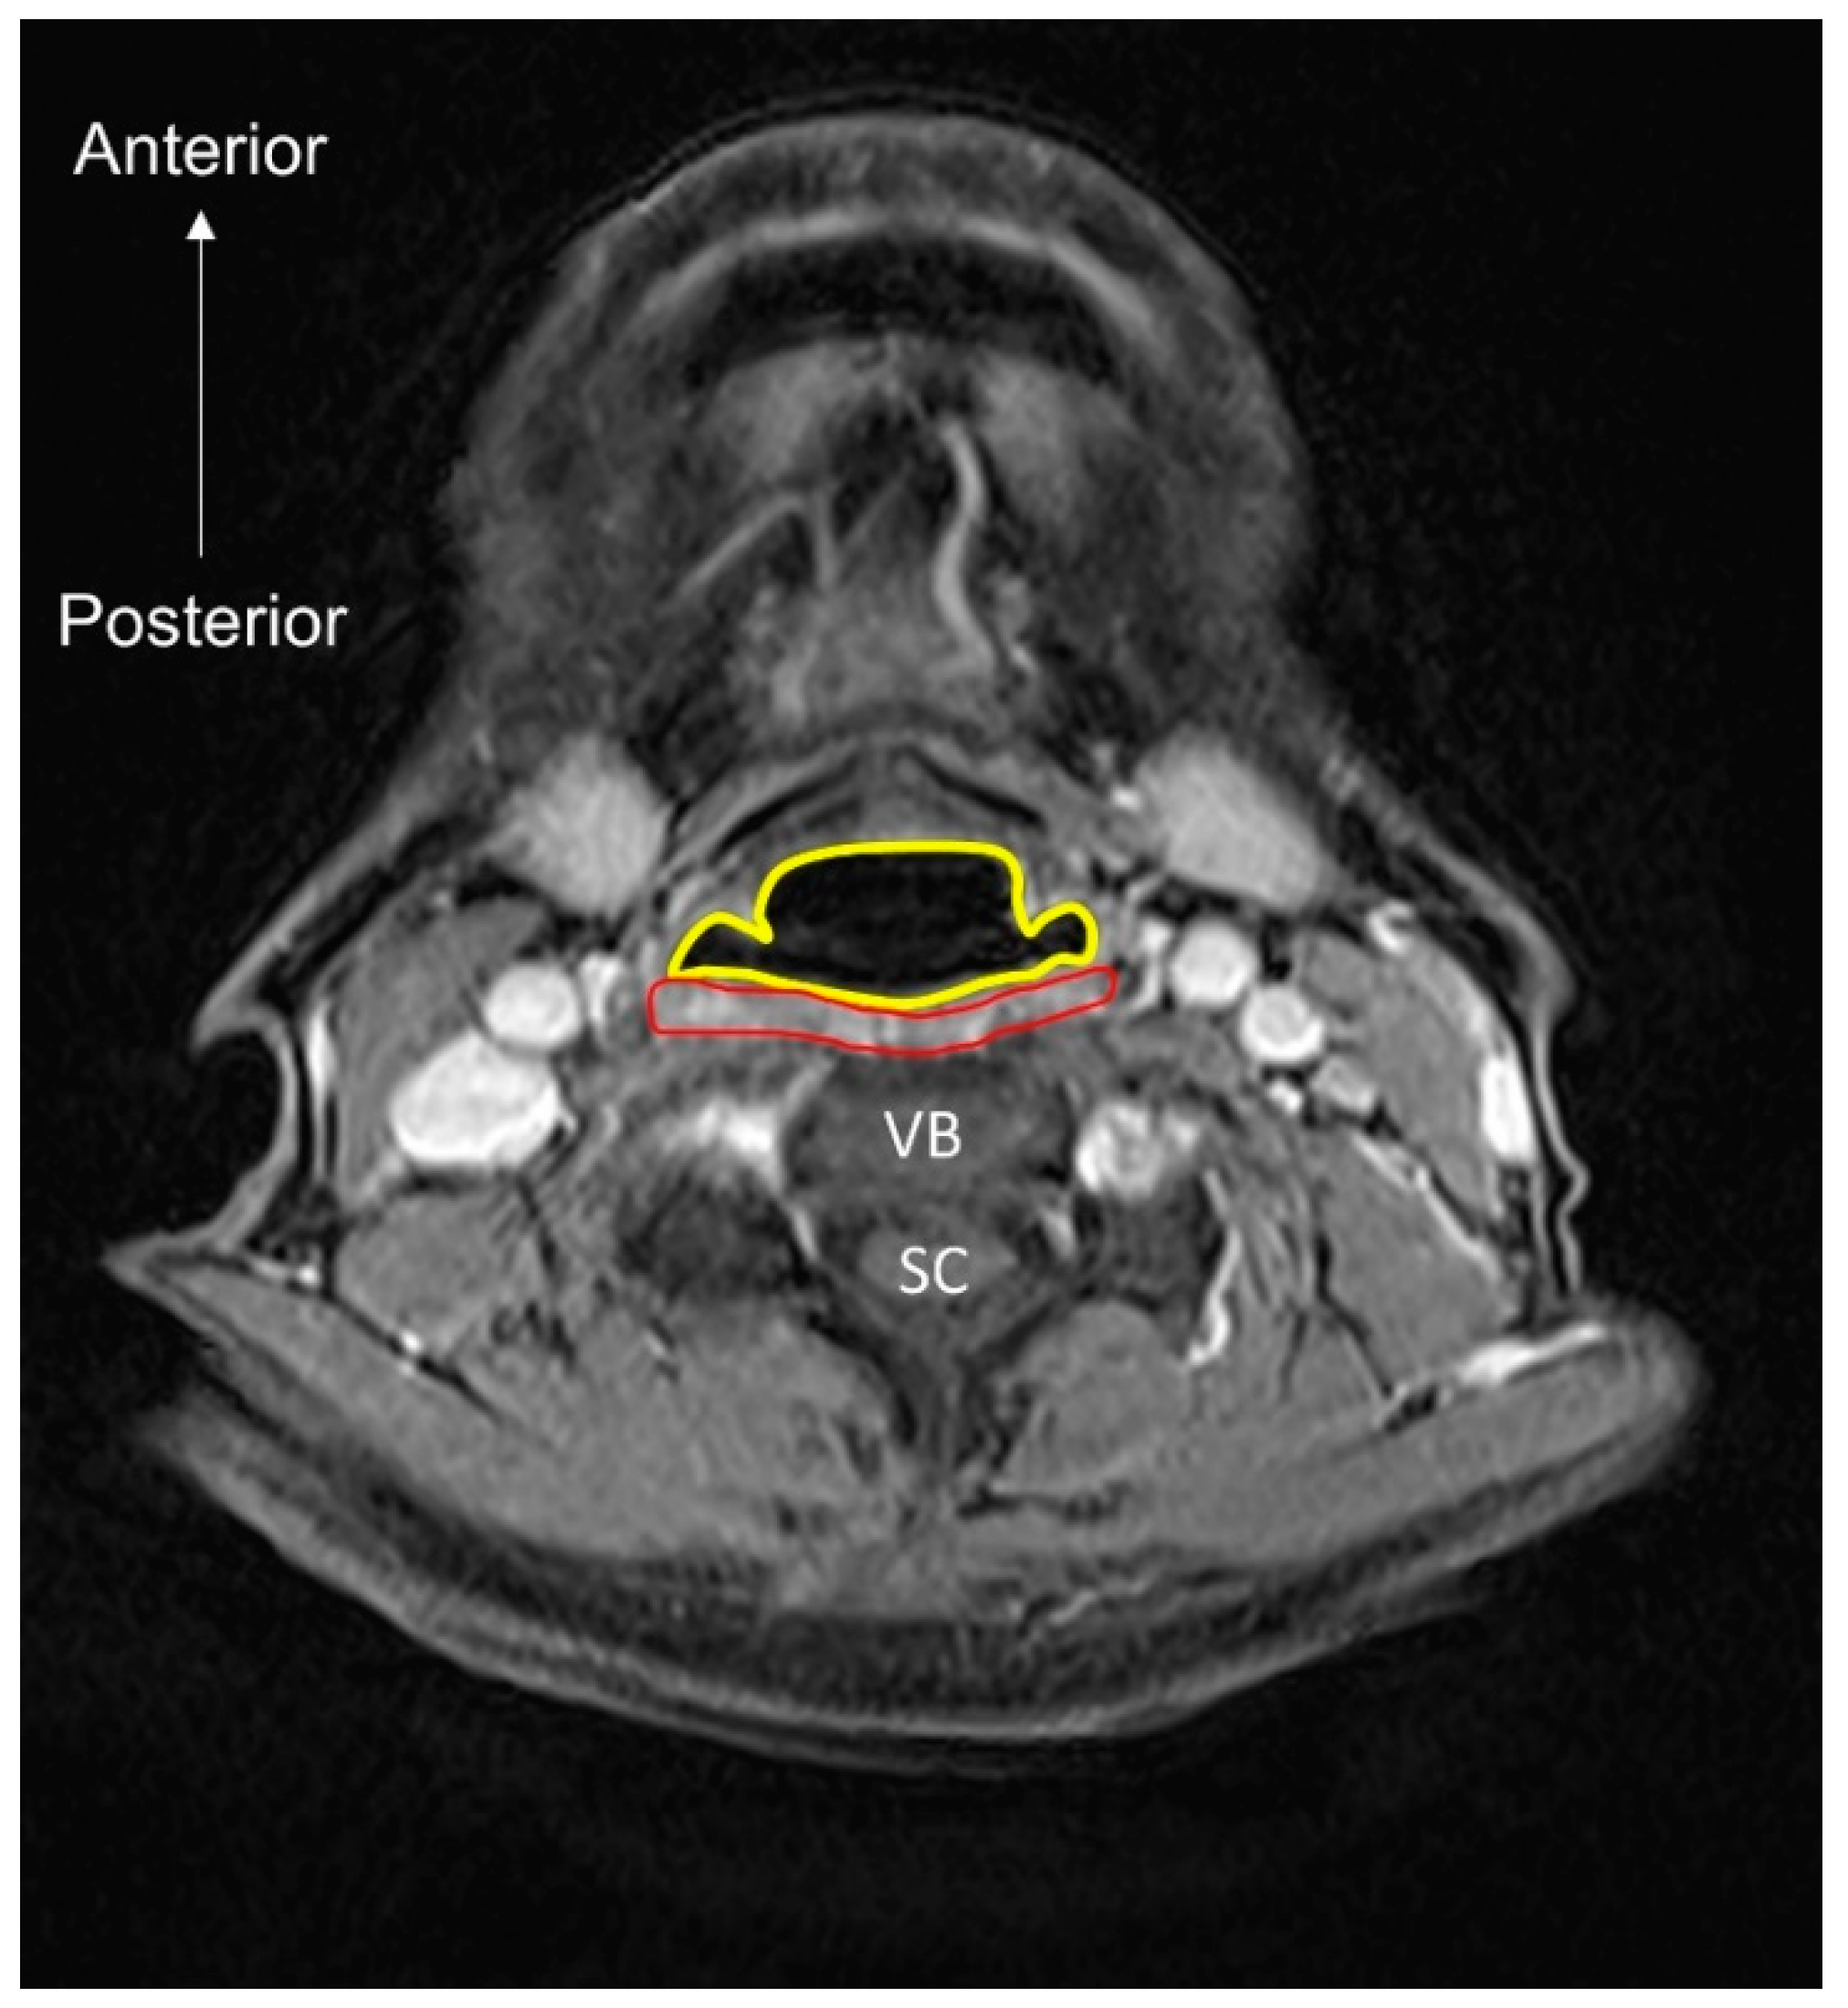

- Nakao, Y.; Uchiyama, Y.; Honda, K.; Yamashita, T.; Saito, S.; Domen, K. Age-related composition changes in swallowing-related muscles: A Dixon MRI study. Aging Clin. Exp. Res. 2021. [Google Scholar] [CrossRef]

- Nakao, Y.; Yamashita, T.; Honda, K.; Katsuura, T.; Hama, Y.; Nakamura, Y.; Ando, K.; Ishikura, R.; Kodama, N.; Uchiyama, Y.; et al. Association Among Age-Related Tongue Muscle Abnormality, Tongue Pressure, and Presbyphagia: A 3D MRI Study. Dysphagia 2021, 36, 483–491. [Google Scholar] [CrossRef]